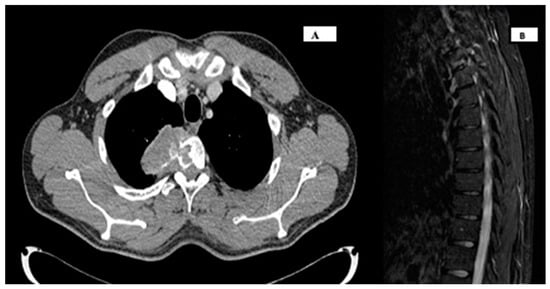

2. Case Report